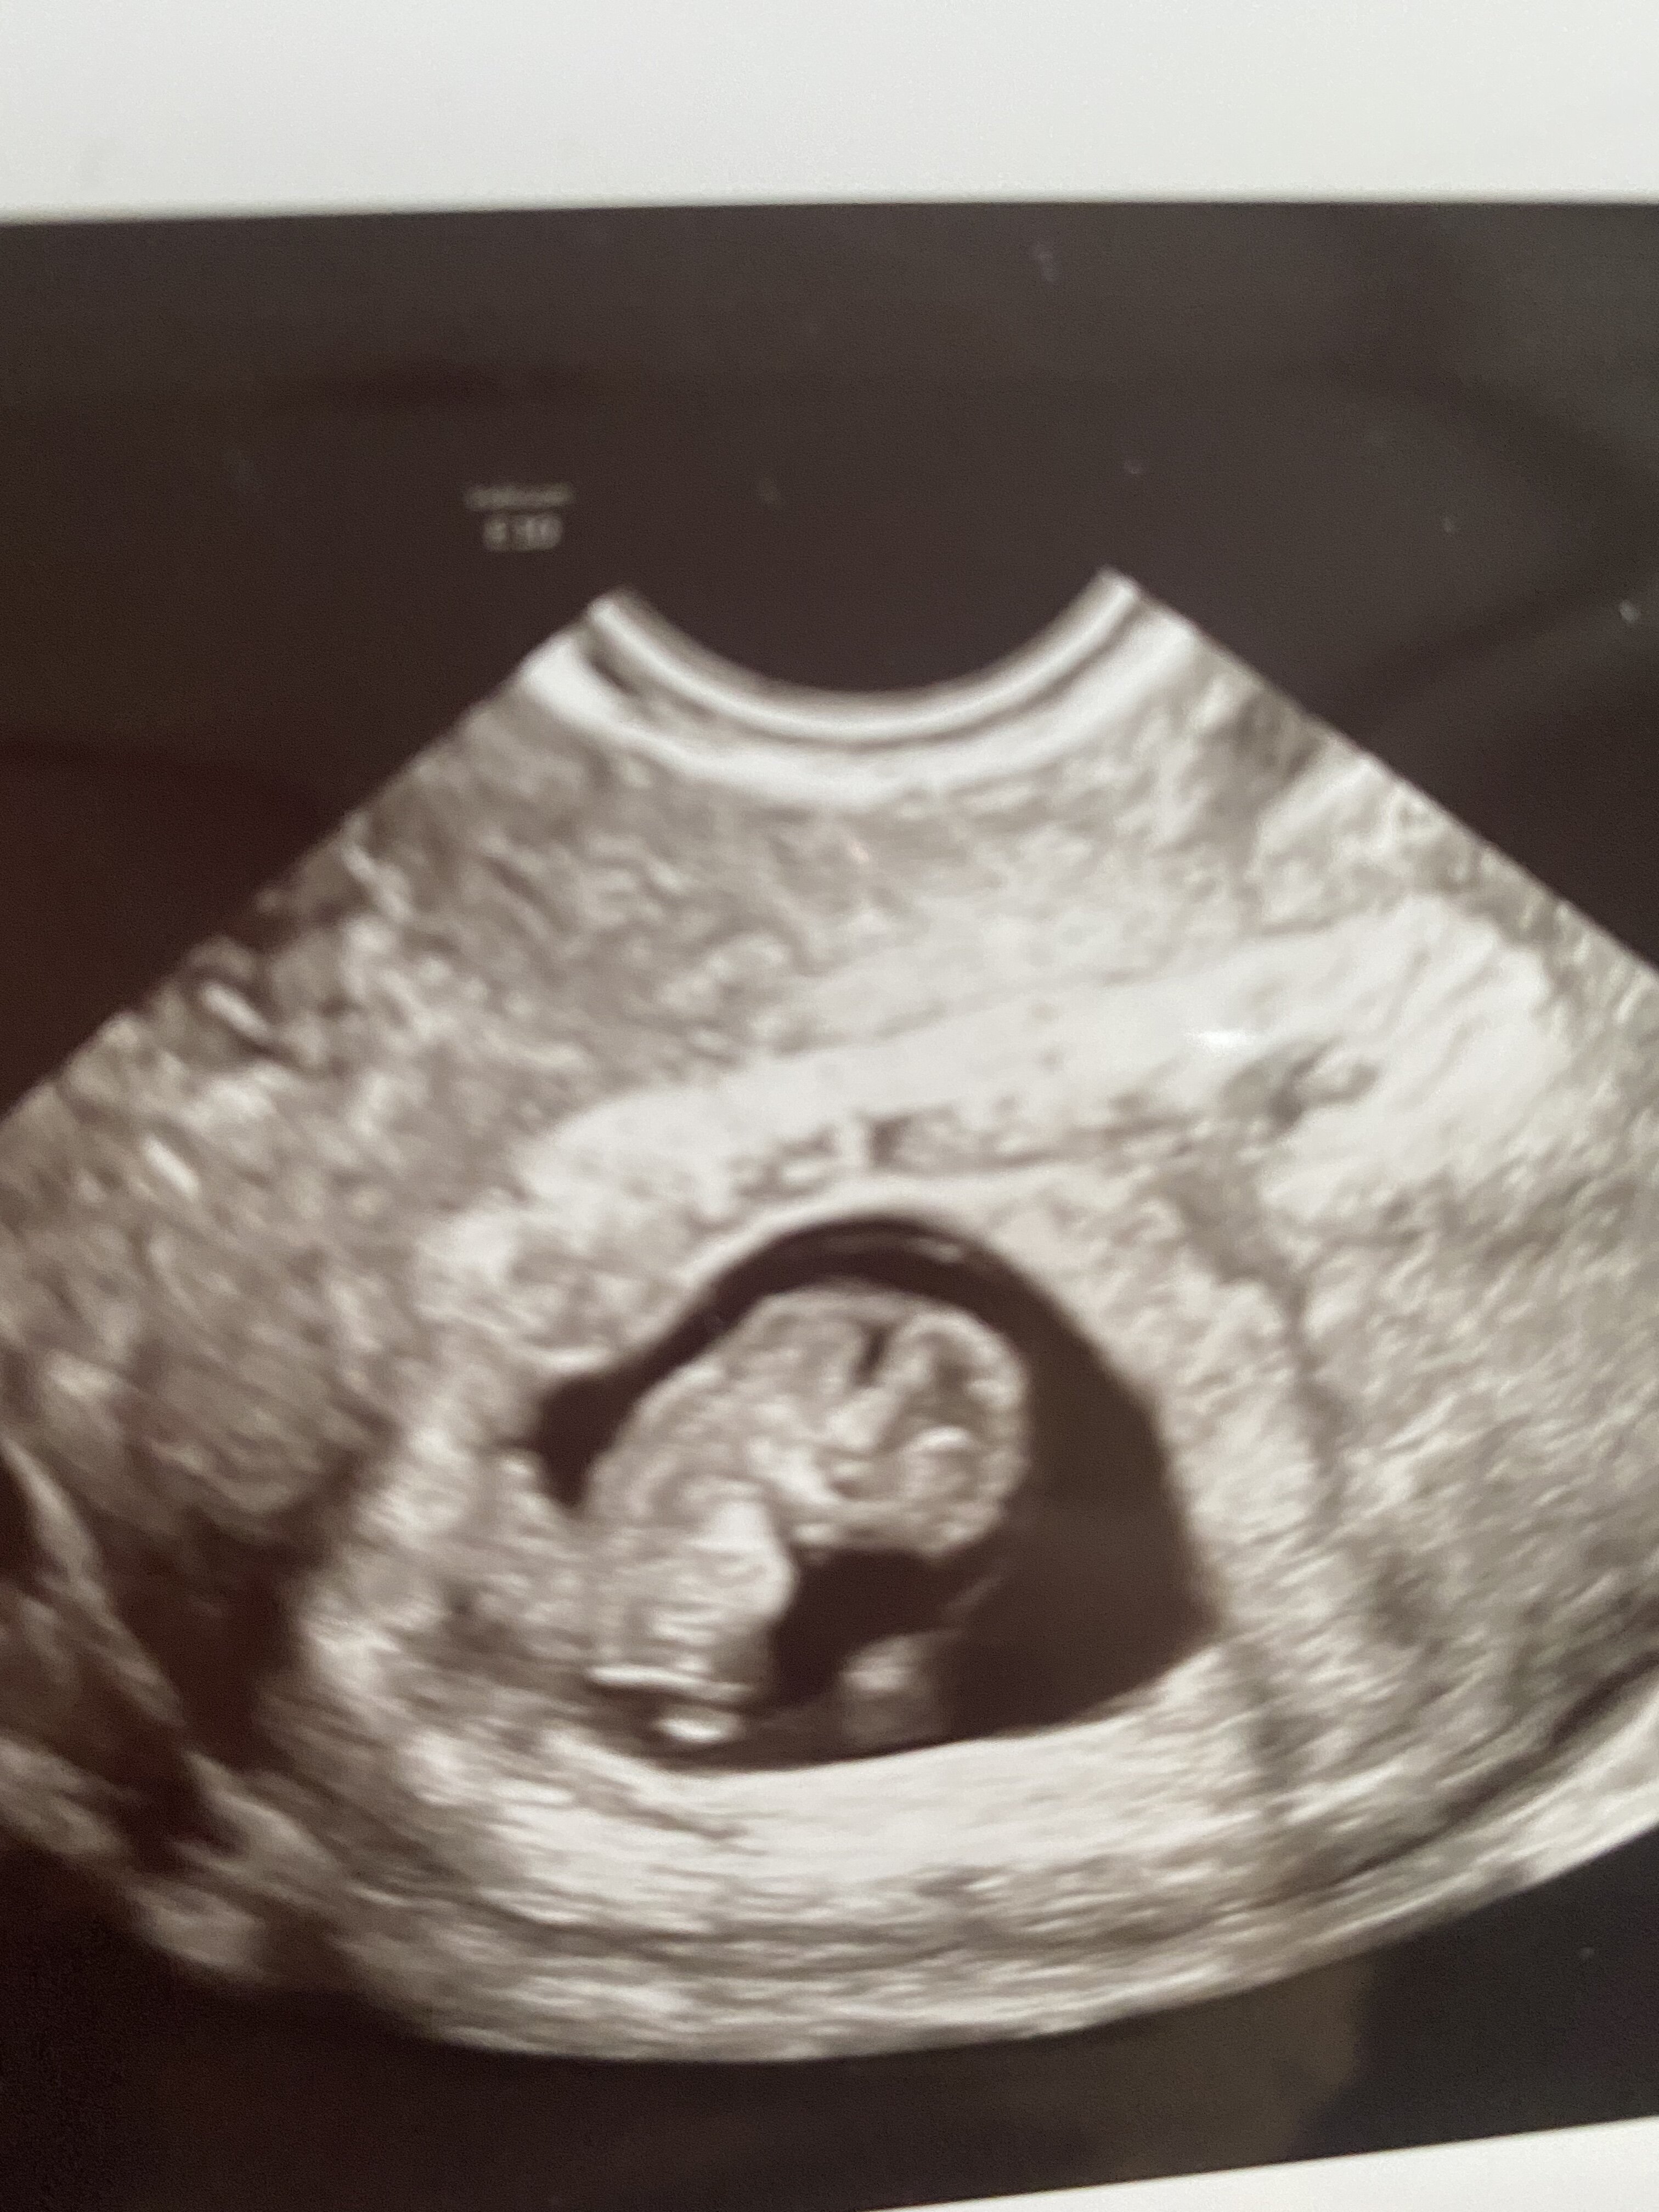

moje bejbi to już mały człowieczek

ma 2,5 cm

machał do mamuni rączka i nóżkami

Serduszko mocno bije

prawie 180 - lekarka mówi ze wszystko w jak najlepszym porządku